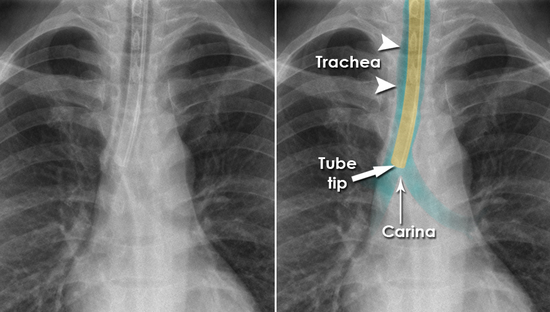

15+ Et Tube Placement Carina Pics. Step by step guidance through placement of et tube in preparation for surgery. The tip of an endotracheal tube (et tube) should be located in the trachea above the carina.

Normally positioned endotracheal tube above the carina ...

Normally positioned endotracheal tube above the carina ... from openi.nlm.nih.gov